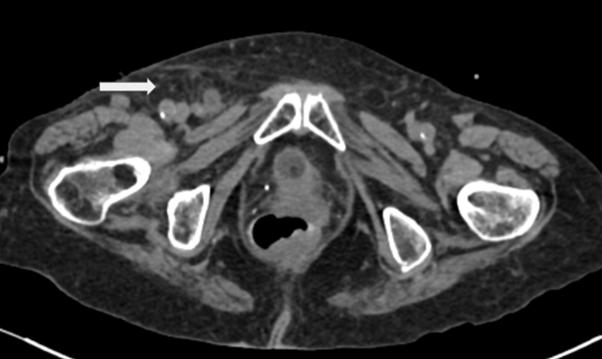

A 93-year-old woman presented to the emergency department with a 1-day history of right lower quadrant abdominal pain that moved into the right groin area. On physical examination, presented with left lower quadrant pain, decreased peristaltic sounds and abdominal distension. Laboratory data demonstrated leukocytosis. Abdominal computed tomography showed an incarcerated right femoral hernia of the appendix with dilatation of the appendix (Figure 1 & 2). She underwent laparoscopic surgery where an incarcerated colon was observed in the internal ring of the right femoral canal (Figure 3 & 4). Appendectomy was performed after reduction (Figure 5). The right femoral hernia of the internal ring was closed with a primary suture (Figure 6 & 7). Pathologic anatomy revealed appendicitis with reactive lymphoid aggregates. From the beginning he was treated with antibiotics, and adequate parenteral fluid management. The postoperative period was adequate, she did not present abdominal symptoms such as pain or nausea. She was discharged 4 days after a successful appendectomy and hernia repair.

Figure 2 Tomography of the abdomen in axial section, showing right femoral hernia with intestinal content.